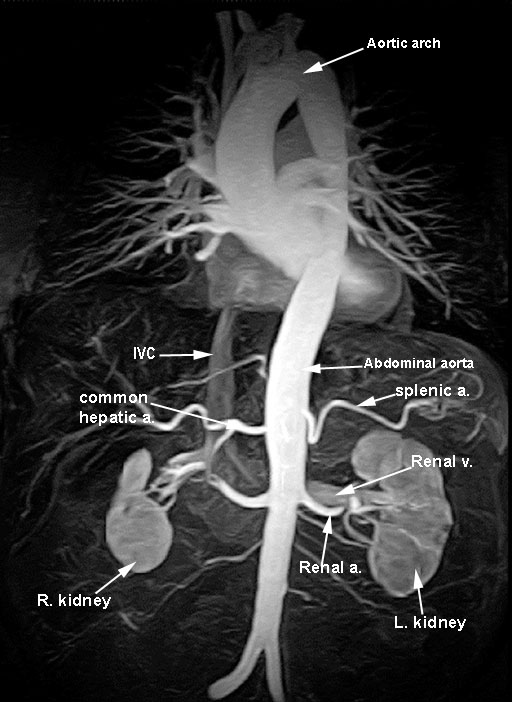

1. Where is the left kidney located in reference to the vertebrae, ribs, and psoas major muscle?

The left kidney is located in the left paravertebral gutter, its hilum facing anterior and medially, against the psoas major muscle. The psoas major slopes laterally as it descends and therefore the lower pole of the kidney is more lateral than the upper. The 11th rib crosses the upper pole of the left kidney and the 12th rib crosses it just above the hilum. The liver pushes the kidney down somewhat so that the right kidney is slightly lower.

The kidney is surrounded by a perirenal fatty capsule, the renal (Gerota's) fascia and pararenal fat. The fat offers no resistance to the hemorrhage, but it was contained in the renal fascia. The renal fascia extends toward the midline and therefore blood was directed toward the abdominal aorta, thus obscuring the margin of the psoas muscle.